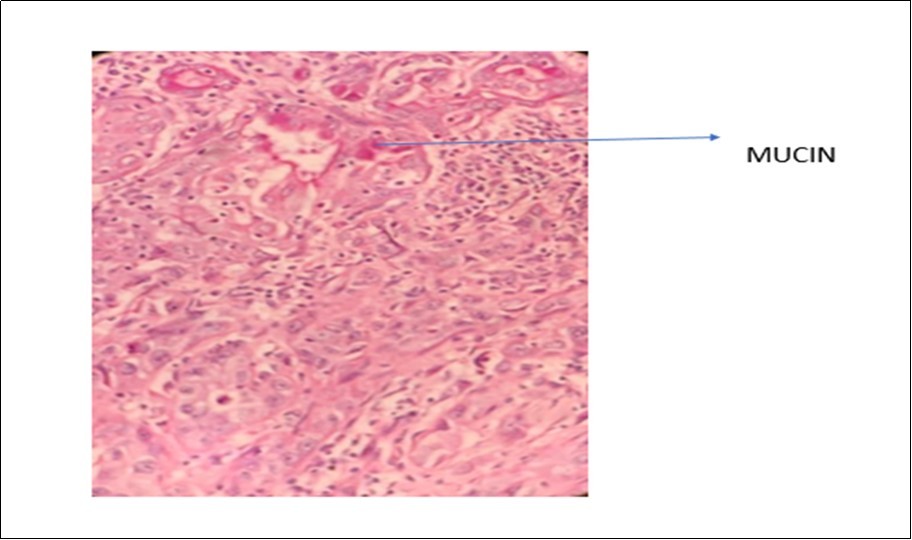

A 70-year-old gentleman, ex-smoker with no comorbid presented to us with hoarseness for 2 months in duration. He also had occasional shortness of breath. There was no constitutional symptom present. Upon our examination, the patient had soft stridor with hoarseness. There were no palpable neck nodes and laryngeal crepitus was present. On flexible nasopharyngolaryngoscopy, a fungating mass was seen occupying the whole length of the left vocal cord, with the cord in a fixed position. The right vocal cord was mobile. A high tracheostomy was done with direct laryngoscopy showing a supraglottic mass obstructing the laryngeal inlet, which is more confined to the left vocal cord and with extension into the subglottic region. Histopathology reported the mass as in favor of MEC. In microscopy, intraluminal and occasional intracytoplasmic PAS-positive diastase-resistant mucin were demonstrated. [Figure 1 & Figure 2] A contrasted-CT scan showed a huge laryngopharyngeal mass extending from the supraglottic to the infraglottic region, with no significant lymphadenopathy nor distant metastasis. The mass had no clear plane with the left thyroid and arytenoid cartilages. Subsequently, the patient underwent a total laryngectomy, left hemithyroidectomy and bilateral selective neck dissection with the histopathology reporting of high-grade MEC, with the involvement of the right level II neck node. Clinically, this is a T4aN0M0 transglottic tumor. Currently, the patient has completed adjuvant radiotherapy with monthly follow-ups at our center. He had remained well at six months follow-up.

Figure 2.Photomicrograph show presence of mucin with positivity of mucicarmine stain in MEC of larynx (x40 high power field)

On the other hand, MEC and SCC lesions are quite similar histologically, which can be tricky to establish the correct diagnosis. The presence of the intermediate and mucous cells in MEC tumors is one of the distinguishing features. 8 Performing a mucicarmine stain is also significant in identifying MEC lesions. Besides, immunohistochemistry expression of MUC-type mucin and expression of cytokeratin marker, CK 14 help establish the diagnosis of MEC. 1 As such, intraluminal and occasional intracytoplasmic PAS-positive diastase-resistant mucin were identified in the case discussed, leading to its diagnosis of MEC of the larynx.